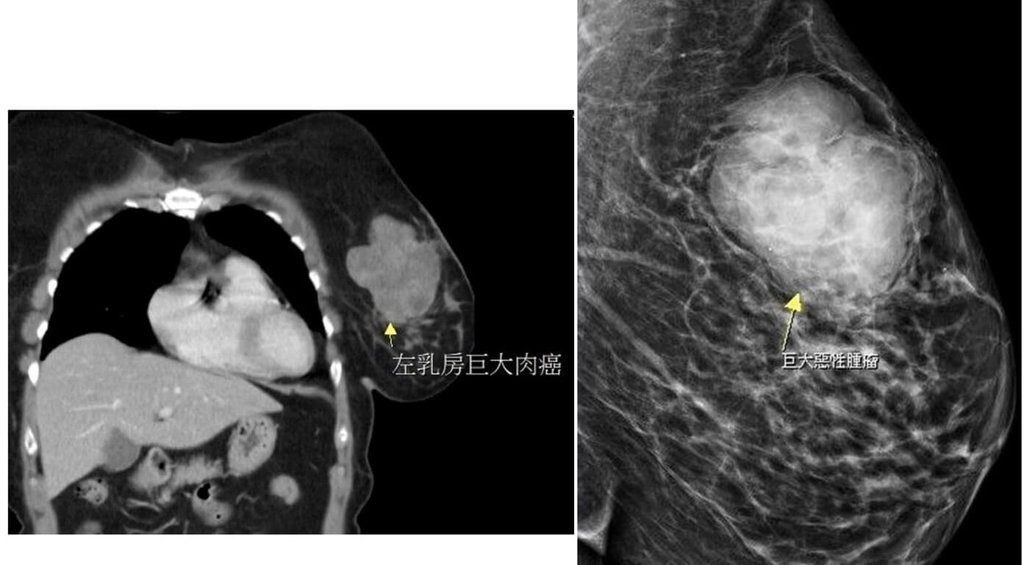

(中央社記者管瑞平苗栗縣29日電)苗栗有婦人單側乳房出現硬塊,就醫檢查出近10公分腫瘤,手術切除病理報告非臨床常見的乳腺癌,而是發生率低且罕見出現在乳房部位的肉癌,醫師提醒身體有異狀務必儘早就醫。

這名56歲黃姓婦人數月來感到左側乳房摸起來有異狀,起初不以為意,直到近日明顯摸到硬塊而且會疼痛才就醫,經超音波檢查已是將近10公分大的腫瘤,大幅增加治療困難度,所幸術後恢復良好,病理報告也證實腫瘤已切除乾淨,持續密集追蹤狀況。